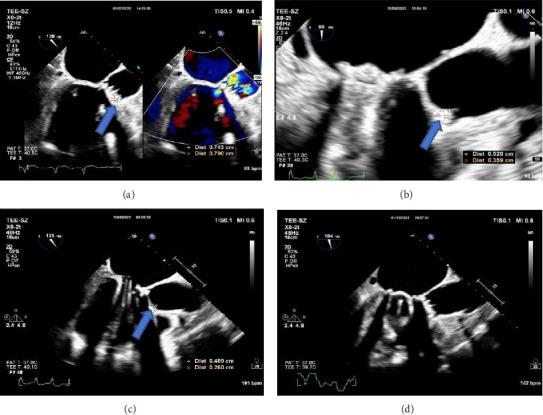

Psittacosis is a zoonotic disease caused by Chlamydia psittaci and is commonly found in birds and poultry. Human infection is uncommon, and most cases are sporadic. Infection of extrapulmonary organs by Chlamydia psittaci is extremely rare. A rare case of infective endocarditis complicated by pneumonia caused by Chlamydia psittaci was reported, which was diagnosed using metagenomic next-generation sequencing (mNGS). The patient recovered after receiving appropriate anti-infective treatment. Discussion on the pathogenesis, diagnosis, and treatment of this disease based on recent literature reports aimed to improve the prognosis of similar patients and enhance the understanding of clinicians.